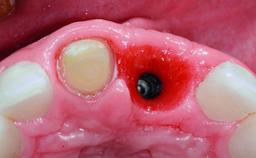

Replacement of a Compromised Upper Right Central Incisor: Hard- and Soft-tissue Augmentation, Late Placement of an RC Bone Level Implant

Bone Augmentation Horizontal|Simultaneous|Staged

Augmentation Materials Xenogenous|Membrane

Placement Protocol Early or late implant placement